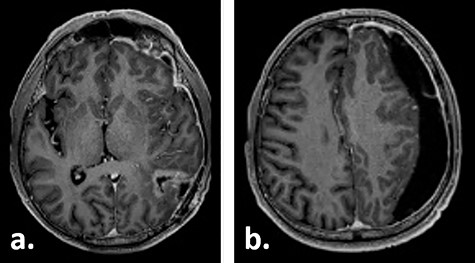

A 67-year-old male patient presented at a local hospital with progressive fatigue, memory and concentration loss, right-sided neglect and weakness as well as gait disturbance. A cerebral MRI scan depicted an inhomogeneous contrast-enhancing, left temporo–parieto–occipital intracerebral tumour invading the trigonum of the left lateral ventricle. The tumour was resected subtotally under 5-ALA fluorescence with a small remnant infiltrating the trigonum of the left lateral ventricle, which was opened intraoperatively (Fig. 1). Histologically, glioblastoma multiforme, WHO IV°, was diagnosed. No molecular analysis was performed.

Gadolinium-enhanced T1-weighted axial MRI of the patient preoperatively (a) and 1 day after the tumour resection (b, c).